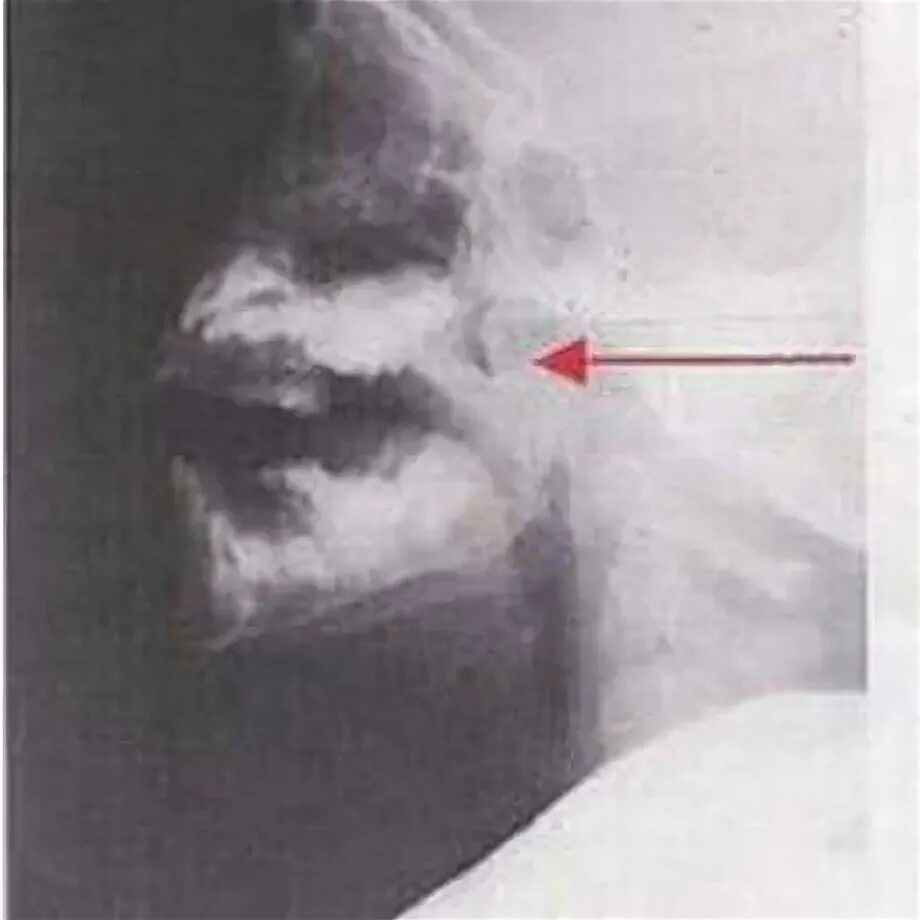

Удалить аденоиды ребенку 3 года